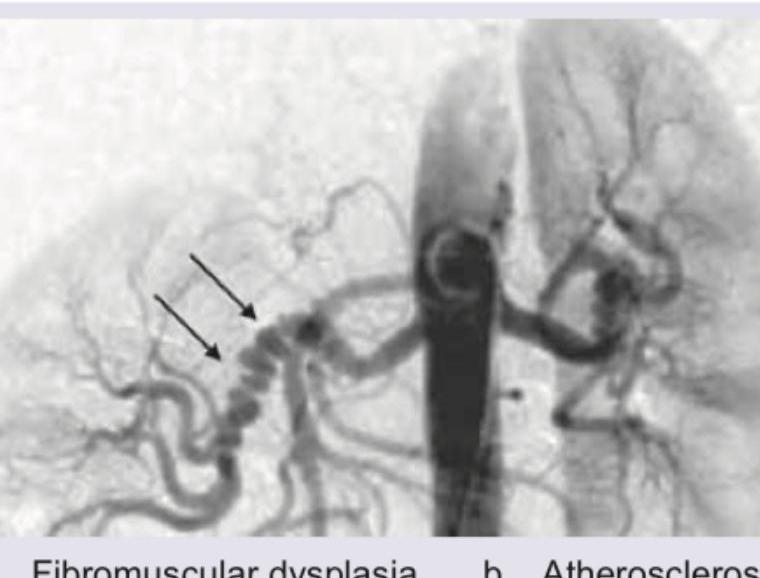

What does the following angiogram in a hypertension patient show?

Explanation: ***Fibromuscular dysplasia*** - The angiogram shows a classic **"string of beads" appearance** in the renal artery, which is pathognomonic for **fibromuscular dysplasia (FMD)**. - This condition is a common cause of **renovascular hypertension**, particularly in **young to middle-aged women**, due to progressive stenosis with alternating areas of arterial dilatation and stenosis. - FMD most commonly affects the **mid to distal portions** of the renal artery. *Atherosclerosis* - **Atherosclerotic renal artery stenosis** typically presents with focal or eccentric narrowing, often with calcifications, and **not** the regular "string of beads" pattern. - It predominantly affects the **ostial or proximal segments** of the renal arteries and is more common in **older patients** with cardiovascular risk factors (smoking, diabetes, hyperlipidemia). *Takayasu arteritis* - **Takayasu arteritis** is a large-vessel vasculitis that causes inflammation and narrowing of the aorta and its major branches, including the renal arteries. - Angiographic findings typically show **long, smooth stenoses** or occlusions, wall thickening, and involvement of the aorta and multiple vessels. - More common in **young Asian women** and presents with constitutional symptoms and vascular insufficiency. *Polyarteritis nodosa* - **Polyarteritis nodosa (PAN)** is a medium-vessel vasculitis that can affect renal arteries and cause hypertension. - Angiographic findings show **multiple microaneurysms** (1-5 mm) scattered throughout medium-sized arteries, creating a "rosary bead" appearance that is **distinct from** the larger, regular "string of beads" of FMD. - Associated with systemic symptoms, livedo reticularis, and multi-organ involvement.

Explanation: ***Fibromuscular dysplasia*** - The CT angiogram shows a **"string of beads" appearance** (indicated by the arrow), which is characteristic of fibromuscular dysplasia (FMD) of the renal artery. - FMD is an **idiopathic, non-inflammatory, non-atherosclerotic condition** that can affect medium-sized arteries, most commonly the renal and carotid arteries, leading to stenosis, aneurysms, or dissections. *Hydronephrosis* - **Hydronephrosis** refers to the **swelling of a kidney** due to a build-up of urine, usually caused by a blockage in the urinary tract. - This image is a CT angiogram visualizing the **renal arteries and aorta**, not the renal collecting system, and therefore cannot directly assess for hydronephrosis. *Duplication of renal collecting system* - **Duplication of the renal collecting system** involves the presence of two separate collecting systems (ureters) draining a single kidney. - This is an arterial phase image focusing on the vascular anatomy and does not provide information about the **collecting system architecture**. *Renal artery stenosis* - While the image does show narrowing in the renal artery (stenosis), simply stating "renal artery stenosis" is a less specific diagnosis. - The **"string of beads" pattern specifically points to fibromuscular dysplasia** as the cause of the stenosis rather than atherosclerosis or other etiologies.